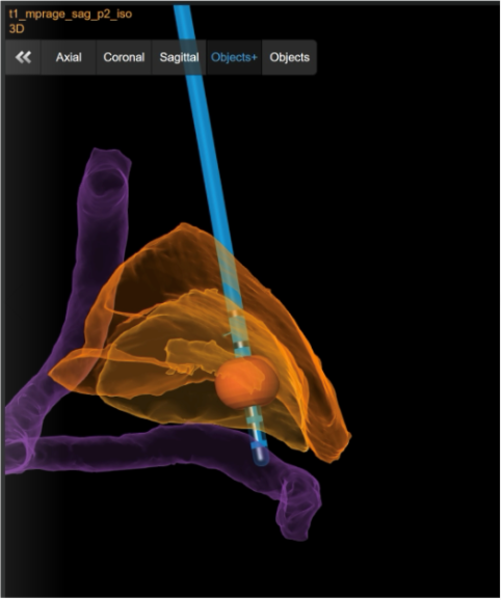

Bei bestimmten Bewegungsstörungen, die nicht oder nicht mehr ausreichend auf eine medikamentöse Therapie ansprechen, ist es möglich, die hierfür verantwortlichen Hirnareale durch die sog. Tiefe Hirnstimulation zu beeinflussen. Hierbei werden feine Elektroden in das Gehirn eingesetzt, um fehlerhafte Nervenstrukturen mit elektrischen Impulsen zu aktivieren oder zu hemmen. Beim Morbus Parkinson, dem essentiellen Tremor oder der Dystonie sind beispielsweise spezifische Hirnareale überaktiv, die dann gezielt durch die Tiefe Hirnstimulation gehemmt und die Symptome wie Zittern oder Muskelsteifigkeit dadurch unterdrückt werden können. Die Hirnregionen selbst bleiben dabei intakt, sodass die Stimulation jederzeit rückgängig gemacht werden kann. Die elektrische Stimulation wird durch einen Impulsgeber gesteuert, der ähnlich wie ein Herzschrittmacher unter die Haut an der Brust der Patient:innen implantiert wird. Die Einstellungen des Impulsgebers lassen sich von außen jederzeit verstellen, sodass die Stimulation an veränderte Bedürfnisse der Patient:innen stets angepasst werden kann.